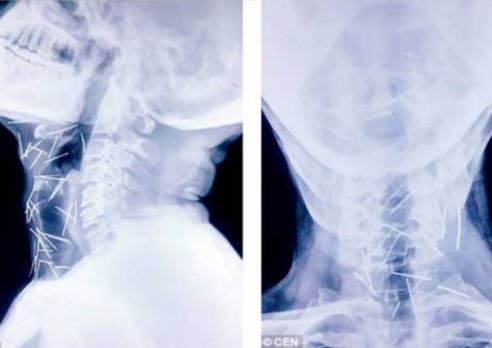

Ảnh chụp X-quang cho thấy kim nằm trong cổ bệnh nhân. Ảnh: DAILY MAIL

Sau khi tiếp tục kiểm tra, các bác sĩ phát hiện có tới 75 cây kim trong cơ thể ông Meena. Trong số 75 cây kim, có 40 cây nằm trong cổ họng, 25 cây ở chân và 2 cây ở cánh tay.